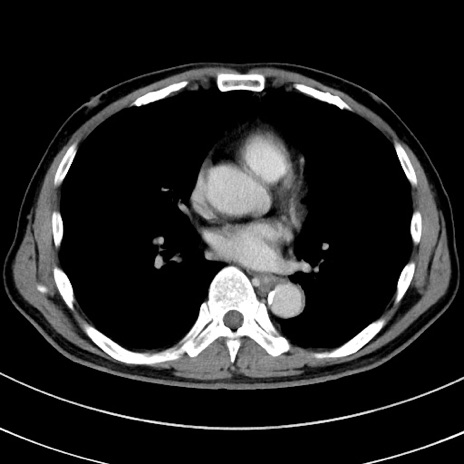

症例8(横断像)

【症例】 60歳代男性

【主訴】 黒色吐物

【現病歴】 4日前から嘔気自覚、2日前の朝食後にも嘔気あり、自分で手で嘔吐反射起こし嘔吐したところ血が混ざっていたため受診。

【既往歴】 5年前汎発性腹膜炎を伴う急性虫垂炎で手術、高血圧、前立腺肥大症、高脂血症

【身体所見】 腹部正中に手術癩痕あり 腹部平坦・軟圧痛なし膨満感あり

【データ】WBC 8400、CRP 4.54